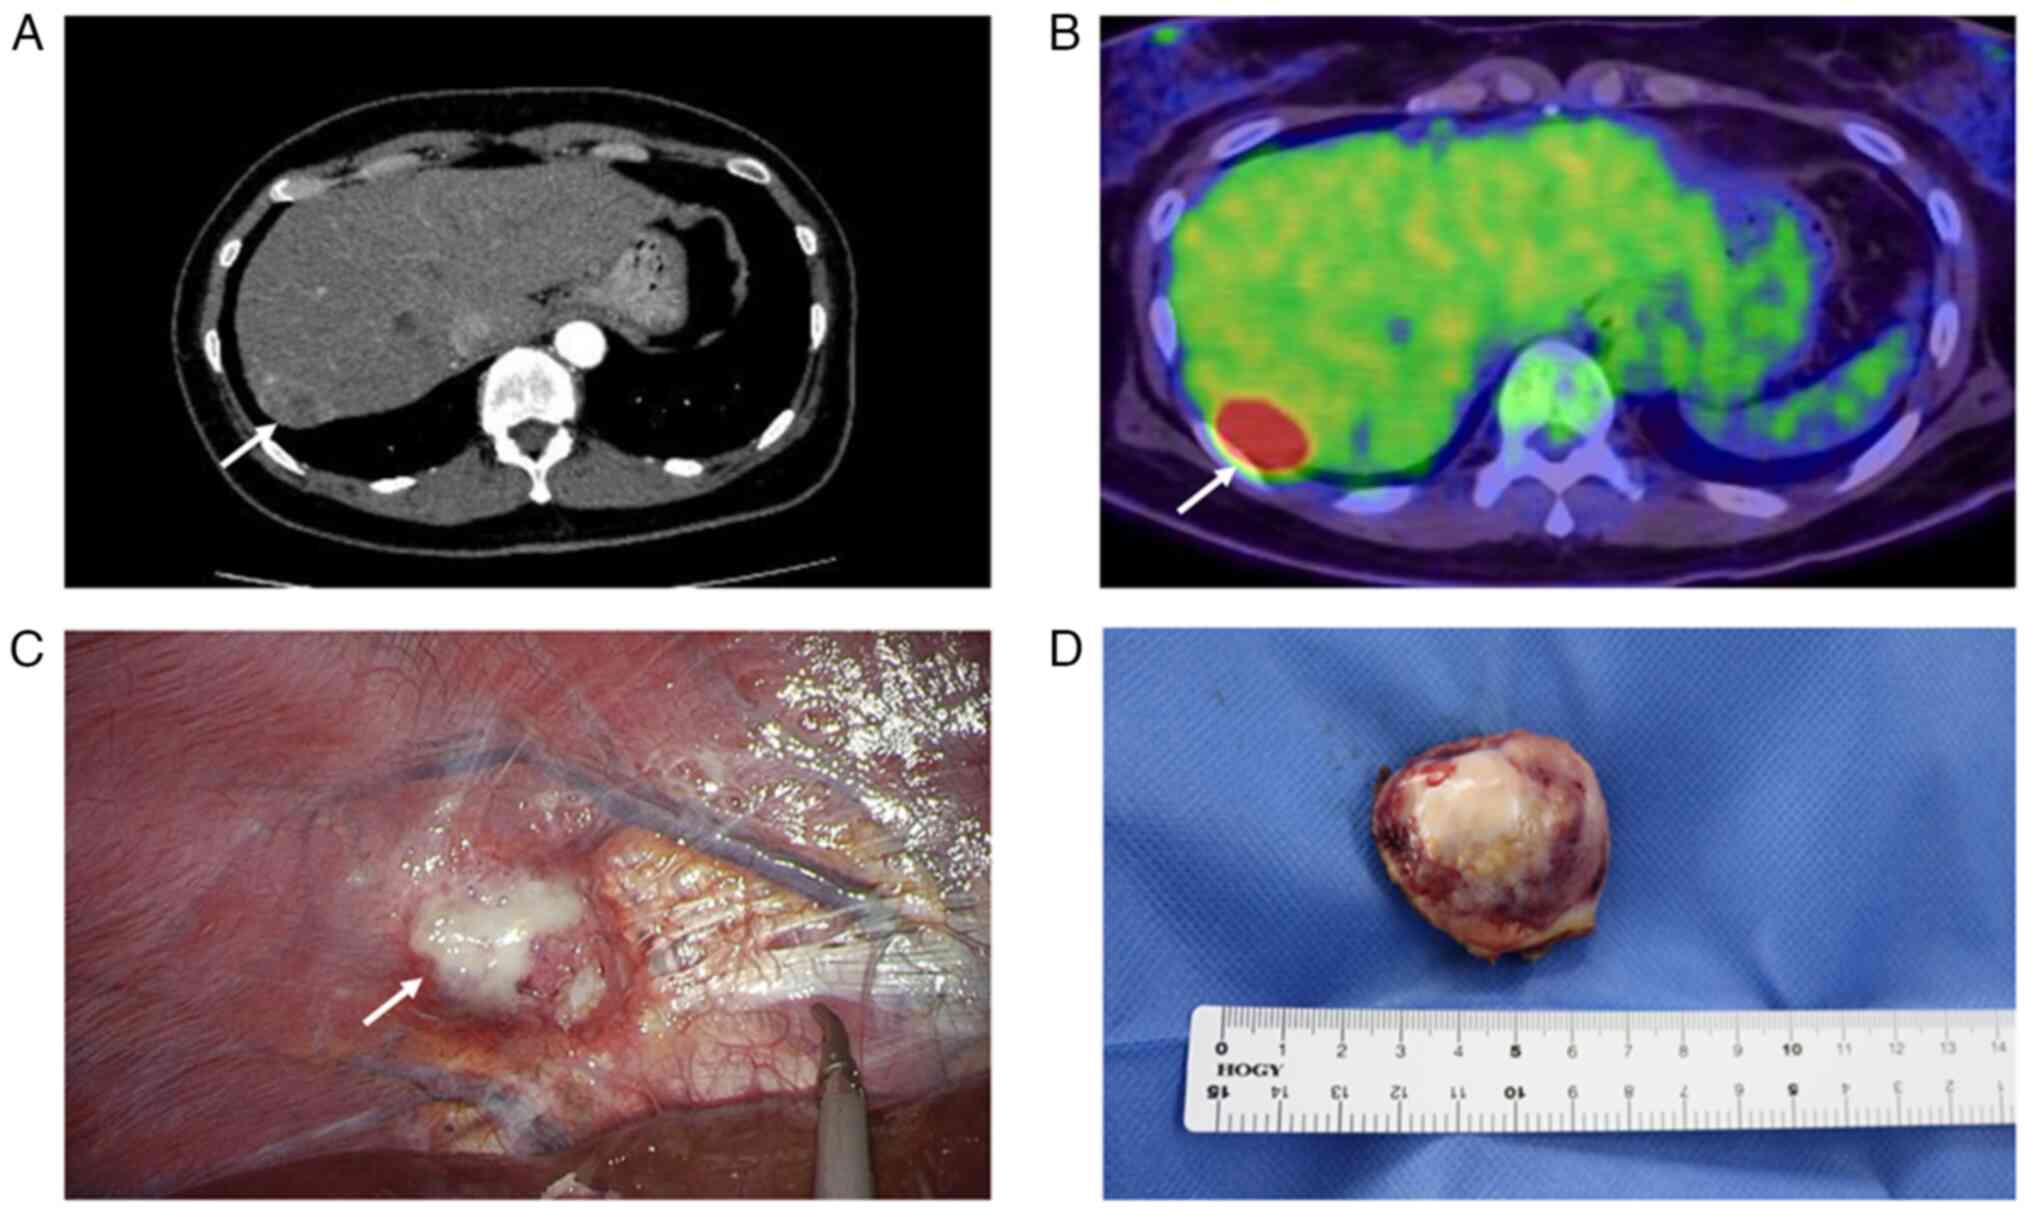

Clear cell carcinoma (CCC) of the diaphragm is rare, with an origin that is reported to be associated with malignant transformation of extraperitoneal endometriosis. Lynch syndrome (LS) is an autosomal dominant hereditary cancer syndrome caused by germline pathogenic variants in one of the DNA mismatch repair (MMR) genes, MLH1, MSH2, MSH6 and PMS2. Women with LS have a significantly increased lifetime risk of endometrial and ovarian cancer. CCC is a common histology of endometriosis‑ and LS‑associated malignancy. The present study describes the case of a 51‑year‑old woman with an intra‑abdominal mass found during a routine physical examination. The patient had undergone total hysterectomy and bilateral adnexectomy for atypical endometrial hyperplasia (AEH) and ovarian endometriosis, respectively, 3 years previously. Enhanced computed tomography showed a mass on the surface of the liver. Laparoscopic examination of the abdominal cavity revealed a tumor on the underside of the right diaphragm, which was then surgically excised. Pathological examination of the excised tumor, along with immunohistochemistry, led to a diagnosis of CCC. Since LS was suspected due to the genetic family history of the patient, microsatellite instability analysis was performed on the diaphragmatic tumor, and the results were positive. Immunohistochemistry was performed for MMR proteins in AEH and CCC cells, both of which revealed loss of MSH2 and MSH6 expression. Following detailed genetic counseling, genetic testing of MMR genes was performed, revealing a germline pathogenic variant in MSH2 (c.1000C>T, p.Gln344*), thus confirming the diagnosis of LS. To the best of our knowledge, this is the first case report of concurrent diaphragmatic CCC and LS. Patients with LS and endometriosis are at risk of developing ovarian cancer or intra‑abdominal malignant tumors. In addition, immunohistochemistry screening for MMR proteins should be considered in patients with AEH and a family history of LS‑related cancer, to enable early clinical intervention in cases of endometrial cancer.

Figure 1